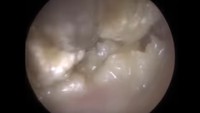

Kotoran telinga ini berwarna putih namun sedikit mengeras. (Foto: YouTube)